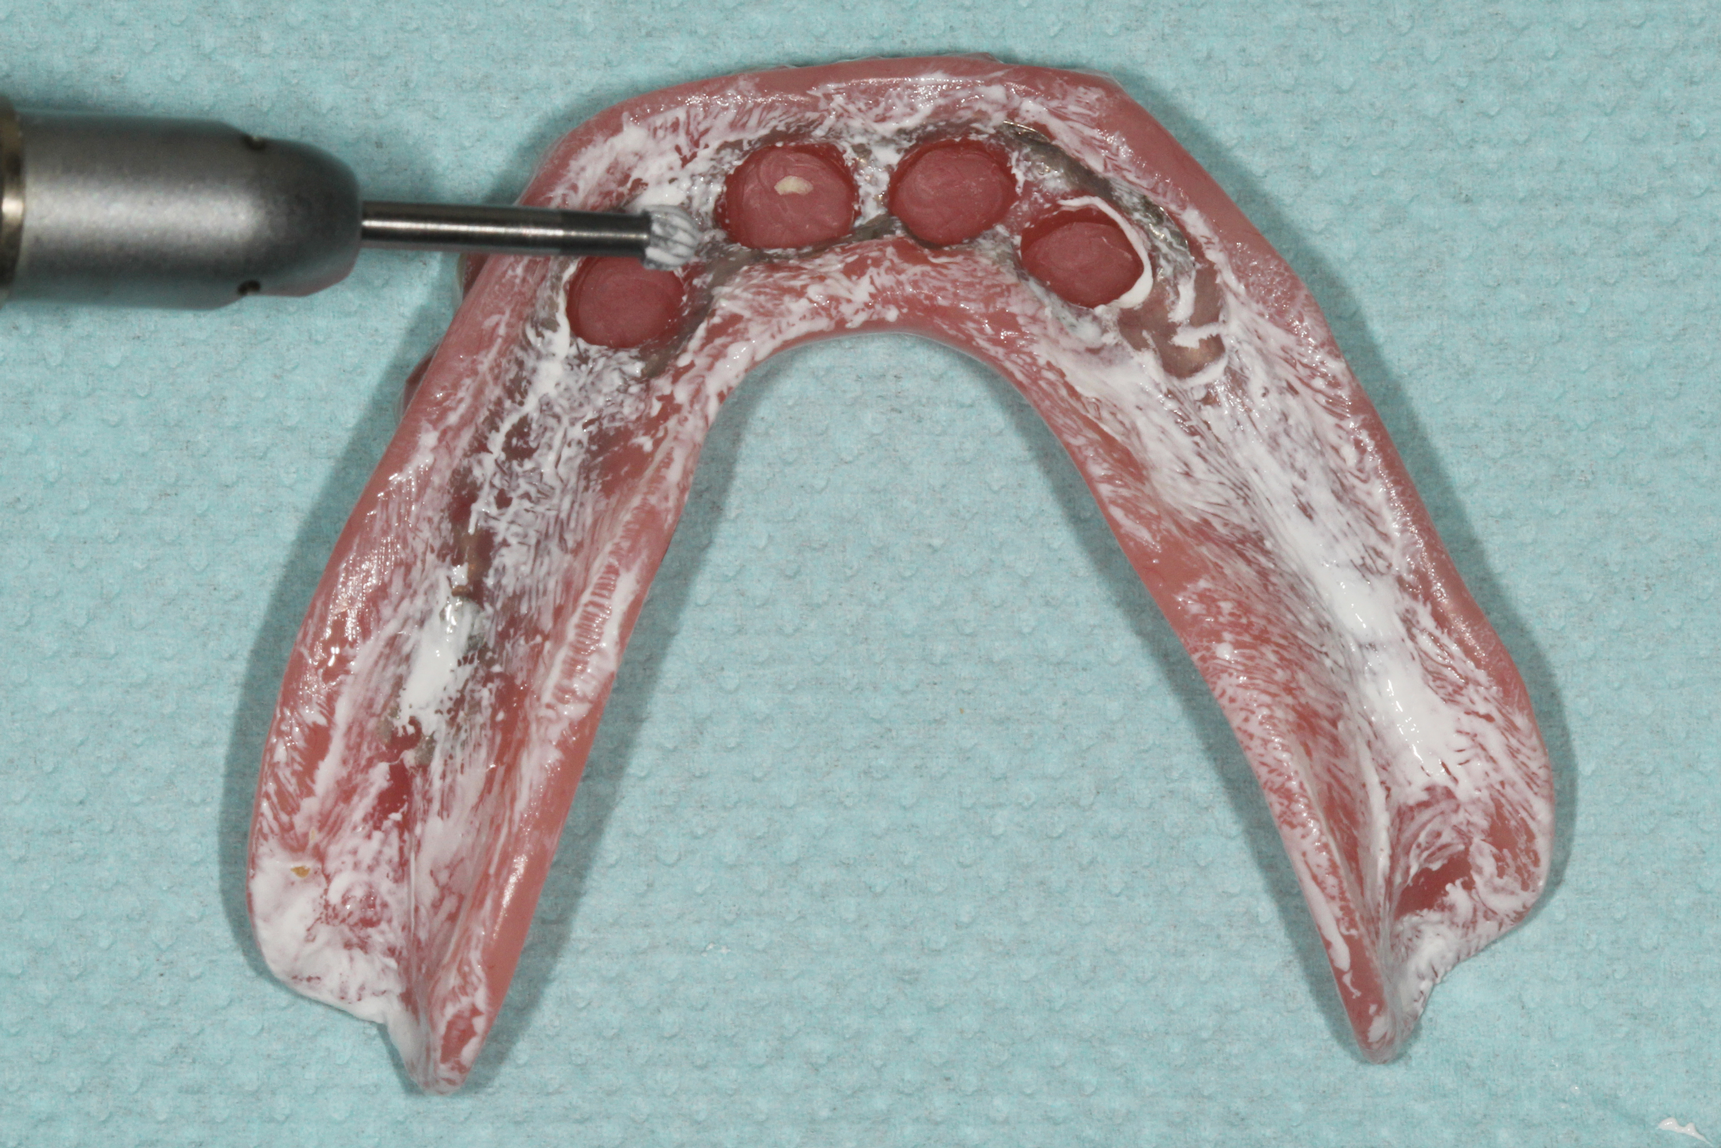

1.) Pretreatment occlusal view of the patient’s mandibular arch showing four existing implants with overdenture attachments.

Figure 1

(3.) Intaglio view of the laboratory processed complete denture with a metal substructure and ideal recesses prepared.

Figure 3

Prosthetic adjustments to the areas of excessive pressure were made using acrylic burs to relieve the areas of paste displacement. First, any pressure areas caused by occlusal forces were adjusted by relieving the areas where heavy pressure was noted with a medium- to large-sized round bur using moderate speed and light force (Figure 8). The anteroposterior pressure areas were adjusted next, and the oblique pressure areas were adjusted last. Both of these pressure areas, which are typically visualized with longer, narrower areas of paste displacement, were adjusted with a tapering acrylic bur using low speed and moderate force. A highspeed handpiece with a large football-shaped carbide bur can assist in adjusting any areas where a metal framework is in excessive contact with the soft tissues.

Once the abutment housings and block-out spacers for the attachment system were placed onto each abutment, the prosthesis was placed onto the edentulous ridge, and a passive fit over the housings was confirmed. The prosthesis was then removed from the mouth, and a vent hole was prepared into each recess using a bur. To process the attachments, a tissue-colored, dual-cure composite resin (CHAIRSIDE® Attachment Processing Material, Zest Dental Solutions [alternatively: Quick Up®, VOCO; Chairside Pick Up Material, Darby Dental Supply]) was placed into the prepared recesses, and the prosthesis was seated onto the edentulous ridge using light finger pressure. Similar to the simulated forces previously used to evaluate the adaptation of the prosthesis, the use of light pressure was to ensure that the prosthesis was passively seated onto the edentulous ridge without overcompressing the soft tissues.